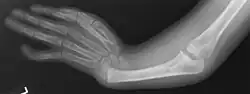

Le syndrome TAR est un syndrome décrit pour la première fois en 1959 et qui associe une thrombopénie et une absence de radius. L'absence de radius est primitif et non pas secondaire à un défaut de vascularisation. Environ 40 % des nouveau-nés décèdent les premiers jours.

Outre les anomalies caractéristiques, on retrouve fréquemment une cardiopathie de type tétralogie de Fallot. Des anomalies des membres inférieurs sont parfois présentes et sévères. L'intolérance au lait de vache est fréquente. Les anomalies plus rares sont : angiome de la face, malformation vasculaire cérébrale et surdité.